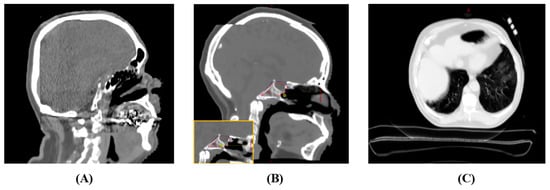

A visual inspection revealed localized discrepancies in certain areas (Figure 8) between the sCT images and the original patient anatomy. Although these instances are infrequent, they may potentially impact the dosimetry results. These discrepancies can be categorized into four primary groups: aliasing artifacts in synthetic CT, distortion of the support couch structure, inconsistencies in HU values within low-density regions, and inaccuracies in replicating the patient’s same-day anatomy.

In assessing synthetic CT image quality, aliasing is most commonly seen near the edge of the CBCT field of view, especially when it overlaps with the original planning CT. This is particularly evident in brain cases for both sCT types. For instance, Figure 8A shows aliasing in the anterior–posterior direction close to the CBCT’s edge, leading to a distorted brain shape towards its posterior. Similarly, the superior–inferior aliasing in Case 2 depicted in Figure 8B induces an isocenter position shift error, yielding skewed dosimetric outcomes. Figure 8C also reveals a substantial deformation of the support couch structure in the DD sCT.

Figure 8. Depictions of discrepancies in synthetic CT images. (A) Case 1—An aliasing effect was observed near the posterior part of the brain where the CBCT FOV edge integrates with the planning CT. (B) Case 2—An aliasing effect was observed in the superior–inferior direction at the merged boundary, leading to an isocenter displacement error (isocenter in yellow circle) (for comparison, the original planning isocenter location is displayed in the bottom left). (C) Case 3—A distorted support couch structure in the DD sCT.